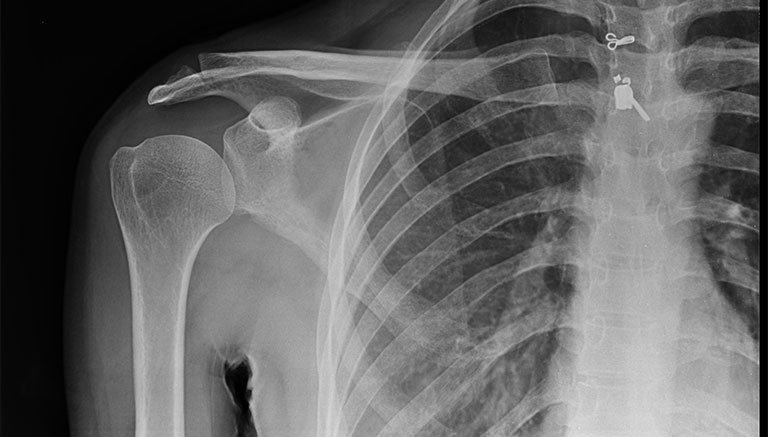

Viêm chu vai hay còn được gọi là viêm quanh khớp vai hay viêm chu vi khớp vai là những trường hợp đau và hạn chế vận động vùng khớp vai với nguyên nhân do các tổn thương phần mềm như: Gân cơ, dây chằng, bao hoạt dịch bao khớp gây ra. Viêm chu vai không hình thành do các tổn thương ở sụn, xương khớp vai và nhiễm trùng.Nguyên nhân thường do thoái hóa, thoát vị các đốt sống cổ, vẹo cổ bẩm sinh, chấn thương do ngồi lâu, cúi lâu, vác nặng sai tư thế. Đa số các trường hợp đều không rõ nguyên nhân.

Để chẩn đoán viêm gân cơ vai chính xác, bác sĩ sẽ yêu cầu được cung cấp thông bệnh sử cũng như những triệu chứng mà người bệnh đang gặp phải.Thông thường, viêm gân cơ vai được chẩn đoán bằng 3 phương pháp:Chụp X-quang, Siêu âm, MRI.